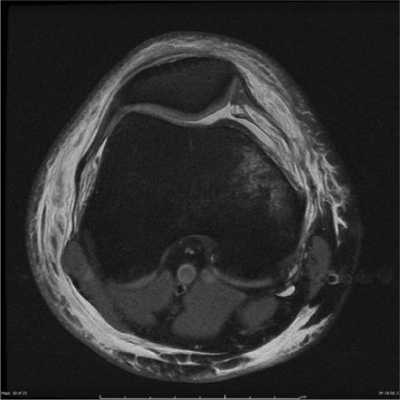

Risonanza magnetica (RM)

La risonanza magnetica rappresenta l’esame di riferimento nella valutazione della lussazione rotulea, soprattutto dopo il primo episodio. La RM consente una valutazione completa delle strutture ossee e dei tessuti molli, fornendo informazioni essenziali per la stratificazione del rischio di recidiva.

In particolare, la RM permette di:

- identificare la lesione del legamento patello-femorale mediale (MPFL)

- valutare la morfologia della troclea femorale

- analizzare la cartilagine femoro-rotulea

- rilevare eventuali lesioni osteocondrali

La presenza di lesioni associate o di significativi fattori anatomici predisponenti può modificare in modo sostanziale l’approccio terapeutico.